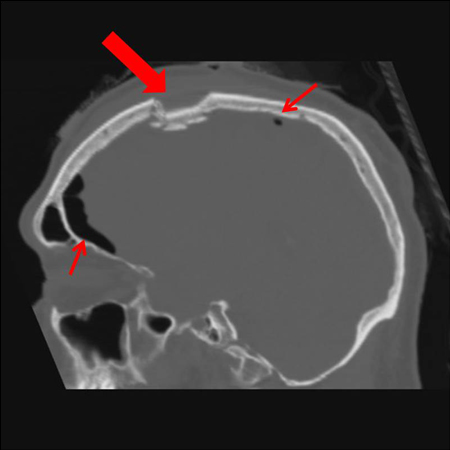

Sagittal CT images of an open, comminuted, depressed skull fracture. Note the associated pneumocephalus (small arrows). The level of depression is greater than the bony table and there are several bone fragments impacted below the inner cortex of the opposing bone (large arrow). Despite lack of underlying associated brain injury this fracture required operative debridement and elevation of the bone fragments. See also the corresponding coronal CT image